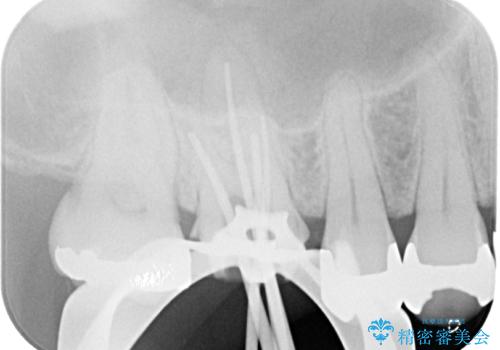

前医ではラバーダムの装着をされていない状態で根管治療を行っていたようで、その他の器具や処置も無菌的環境下であったとは考えにくいため、それが痛みがなかなか引かない原因の一つであると考えられました。

根管治療後に痛みの消失を確認し、オールセラミッククラウンにて補綴治療を行うこととしました。

初回の根管治療時に仮歯を装着しましたが、仮歯を介して食事などを行っても痛みは感じなくなっており、その後は速やかに補綴治療を行いました。